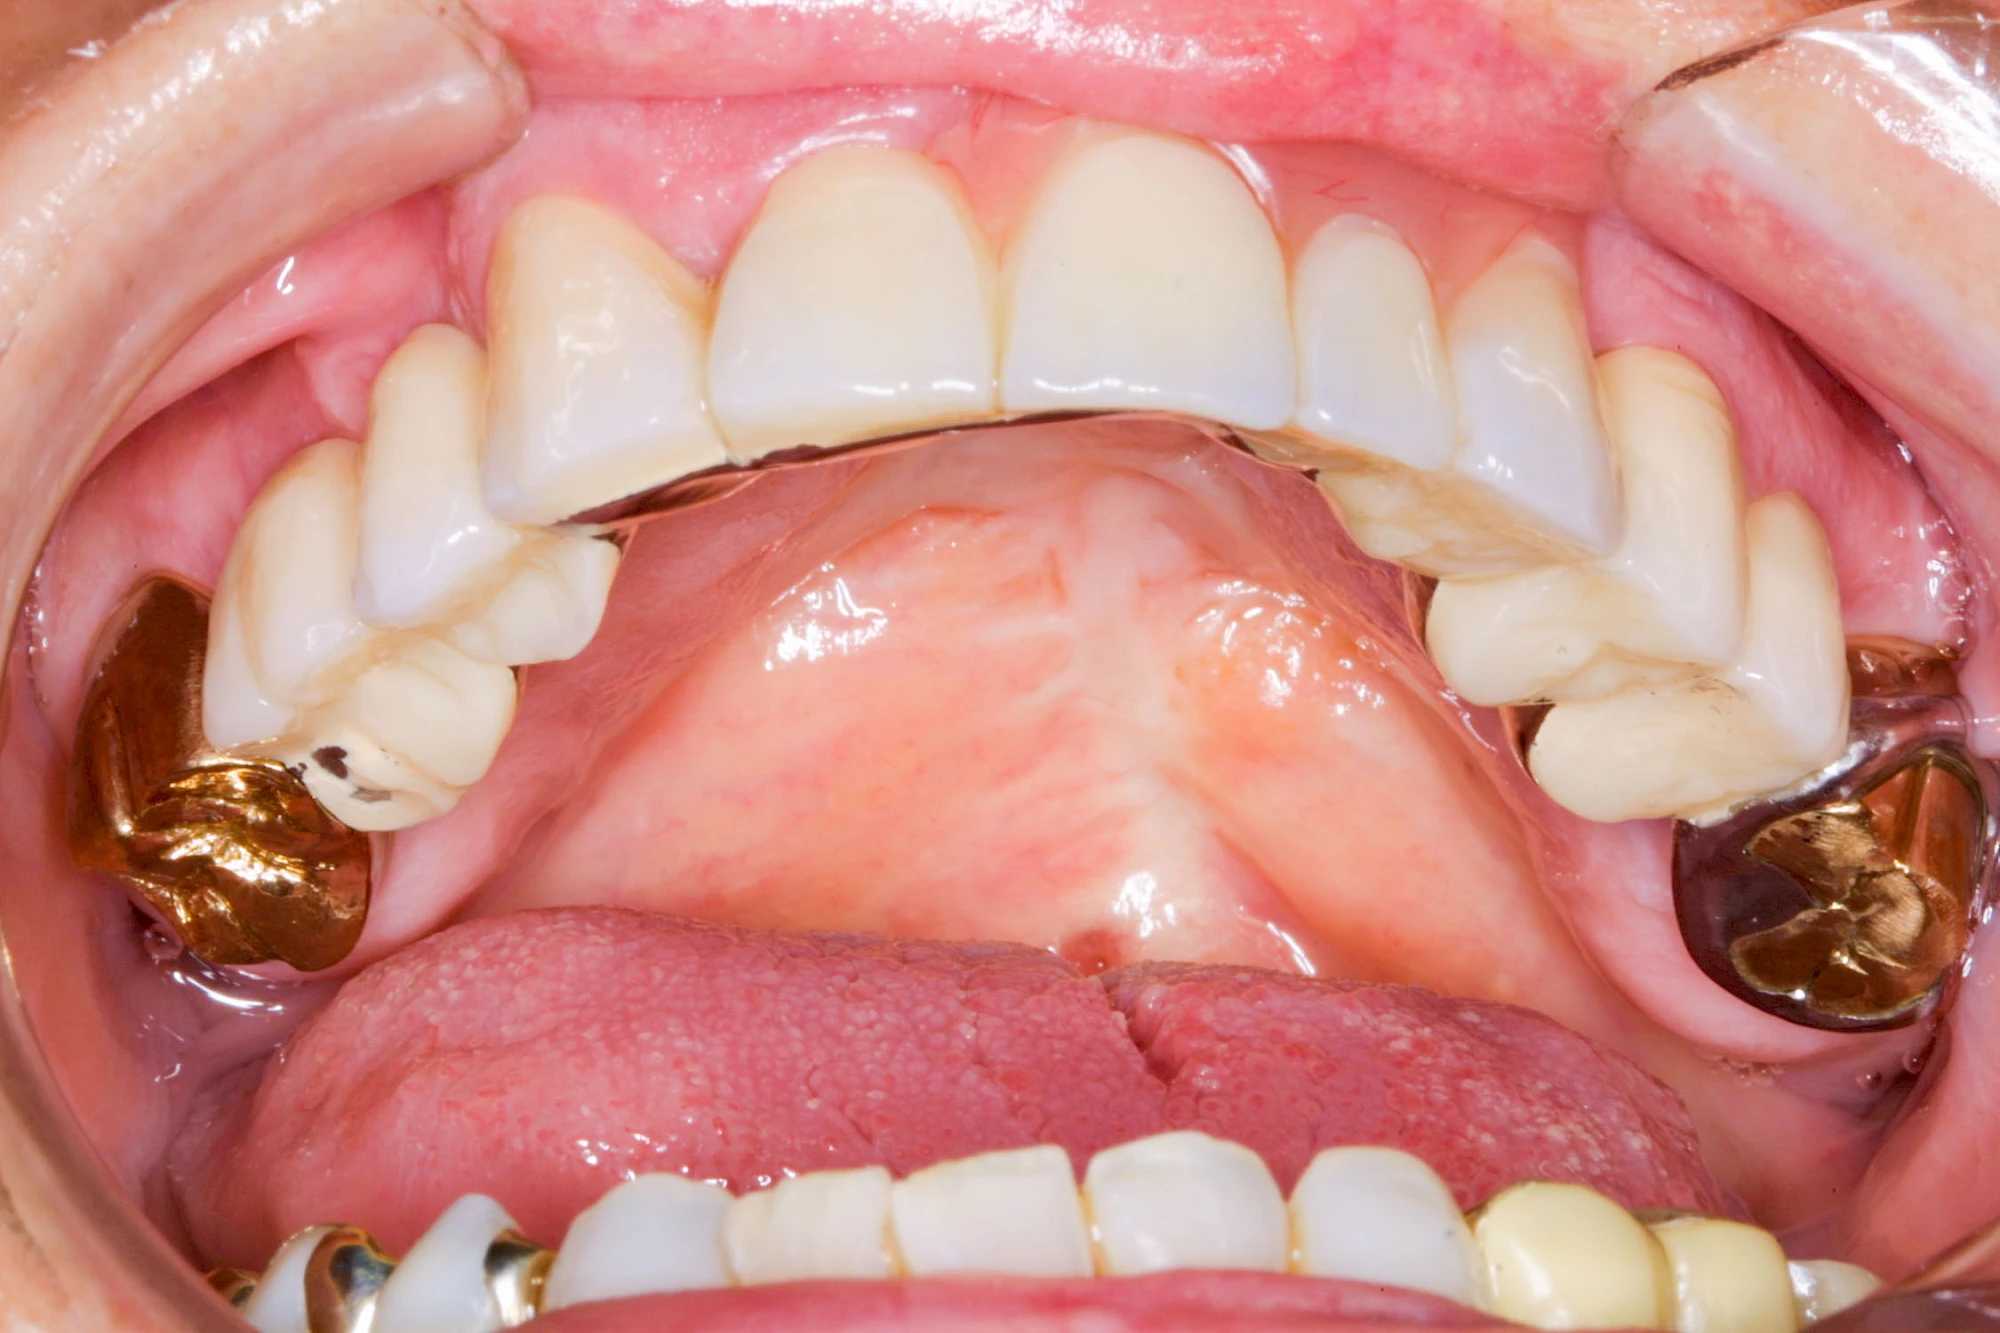

Gehen die Zähne verloren, baut häufig auch der Kieferknochen ab (Knochenschwund). Die Geschwindigkeit und das Ausmaß des Knochenschwundes ist von vielen Faktoren abhängig. Neben der genetischen Veranlagung spielen auch Überbelastungen in Folge, z. B. bei ständigem Knirschen oder Pressen, eine Rolle. Auch wenn Zahnprothesen Tag und Nacht getragen werden, kann die ständige Belastung der Schleimhäute und des Knochens den Knochenschwund beschleunigen.

Aber Achtung: Manche Menschen fühlen sich ohne Zahnprothesen unwohl. Zudem kann es passieren, dass Zahnprothesen (wenn noch eigene Zähne vorhanden sind) nicht mehr passen. Dies gilt vor allem dann, wenn diese Zahnprothesen nicht nur über Nacht, sondern für einen längeren Zeitraum nicht mehr getragen werden.

In jedem Fall sagen die Betroffenen, dass es sich ein paar Minuten komisch anfühlt, wenn sie die Zahnprothesen über Nacht aus dem Mund nehmen und dann morgens wieder einsetzen. Das ist normal und liegt daran, dass die Schleimhäute sich wieder regenerieren. Das ist gut für die Schleimhäute und Knochen im Bereich der Kiefer. Wir gehen ja auch nicht mit Schuhen ins Bett!

In seltenen Fällen schwindet nur der Knochen, aber nicht die bedeckenden Schleimhäute. In diesen Fällen spricht man von einem sogenannten "Schlotterkamm".